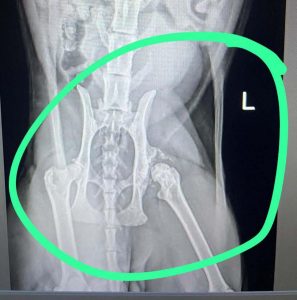

Alle veröffentlichten Bilder stammen aus dem Taunus und entstanden bei Einsätzen ehrenamtlicher Helfer. Darüber hinaus liegen der Redaktion Aufnahmen vor, die gravierende Verletzungen und erhebliches Tierleid dokumentieren. Im Sinne eines verantwortungsvollen Umgangs mit unseren Leser:innen – insbesondere Kindern und sensiblen Personen – verzichten wir auf deren Veröffentlichung.